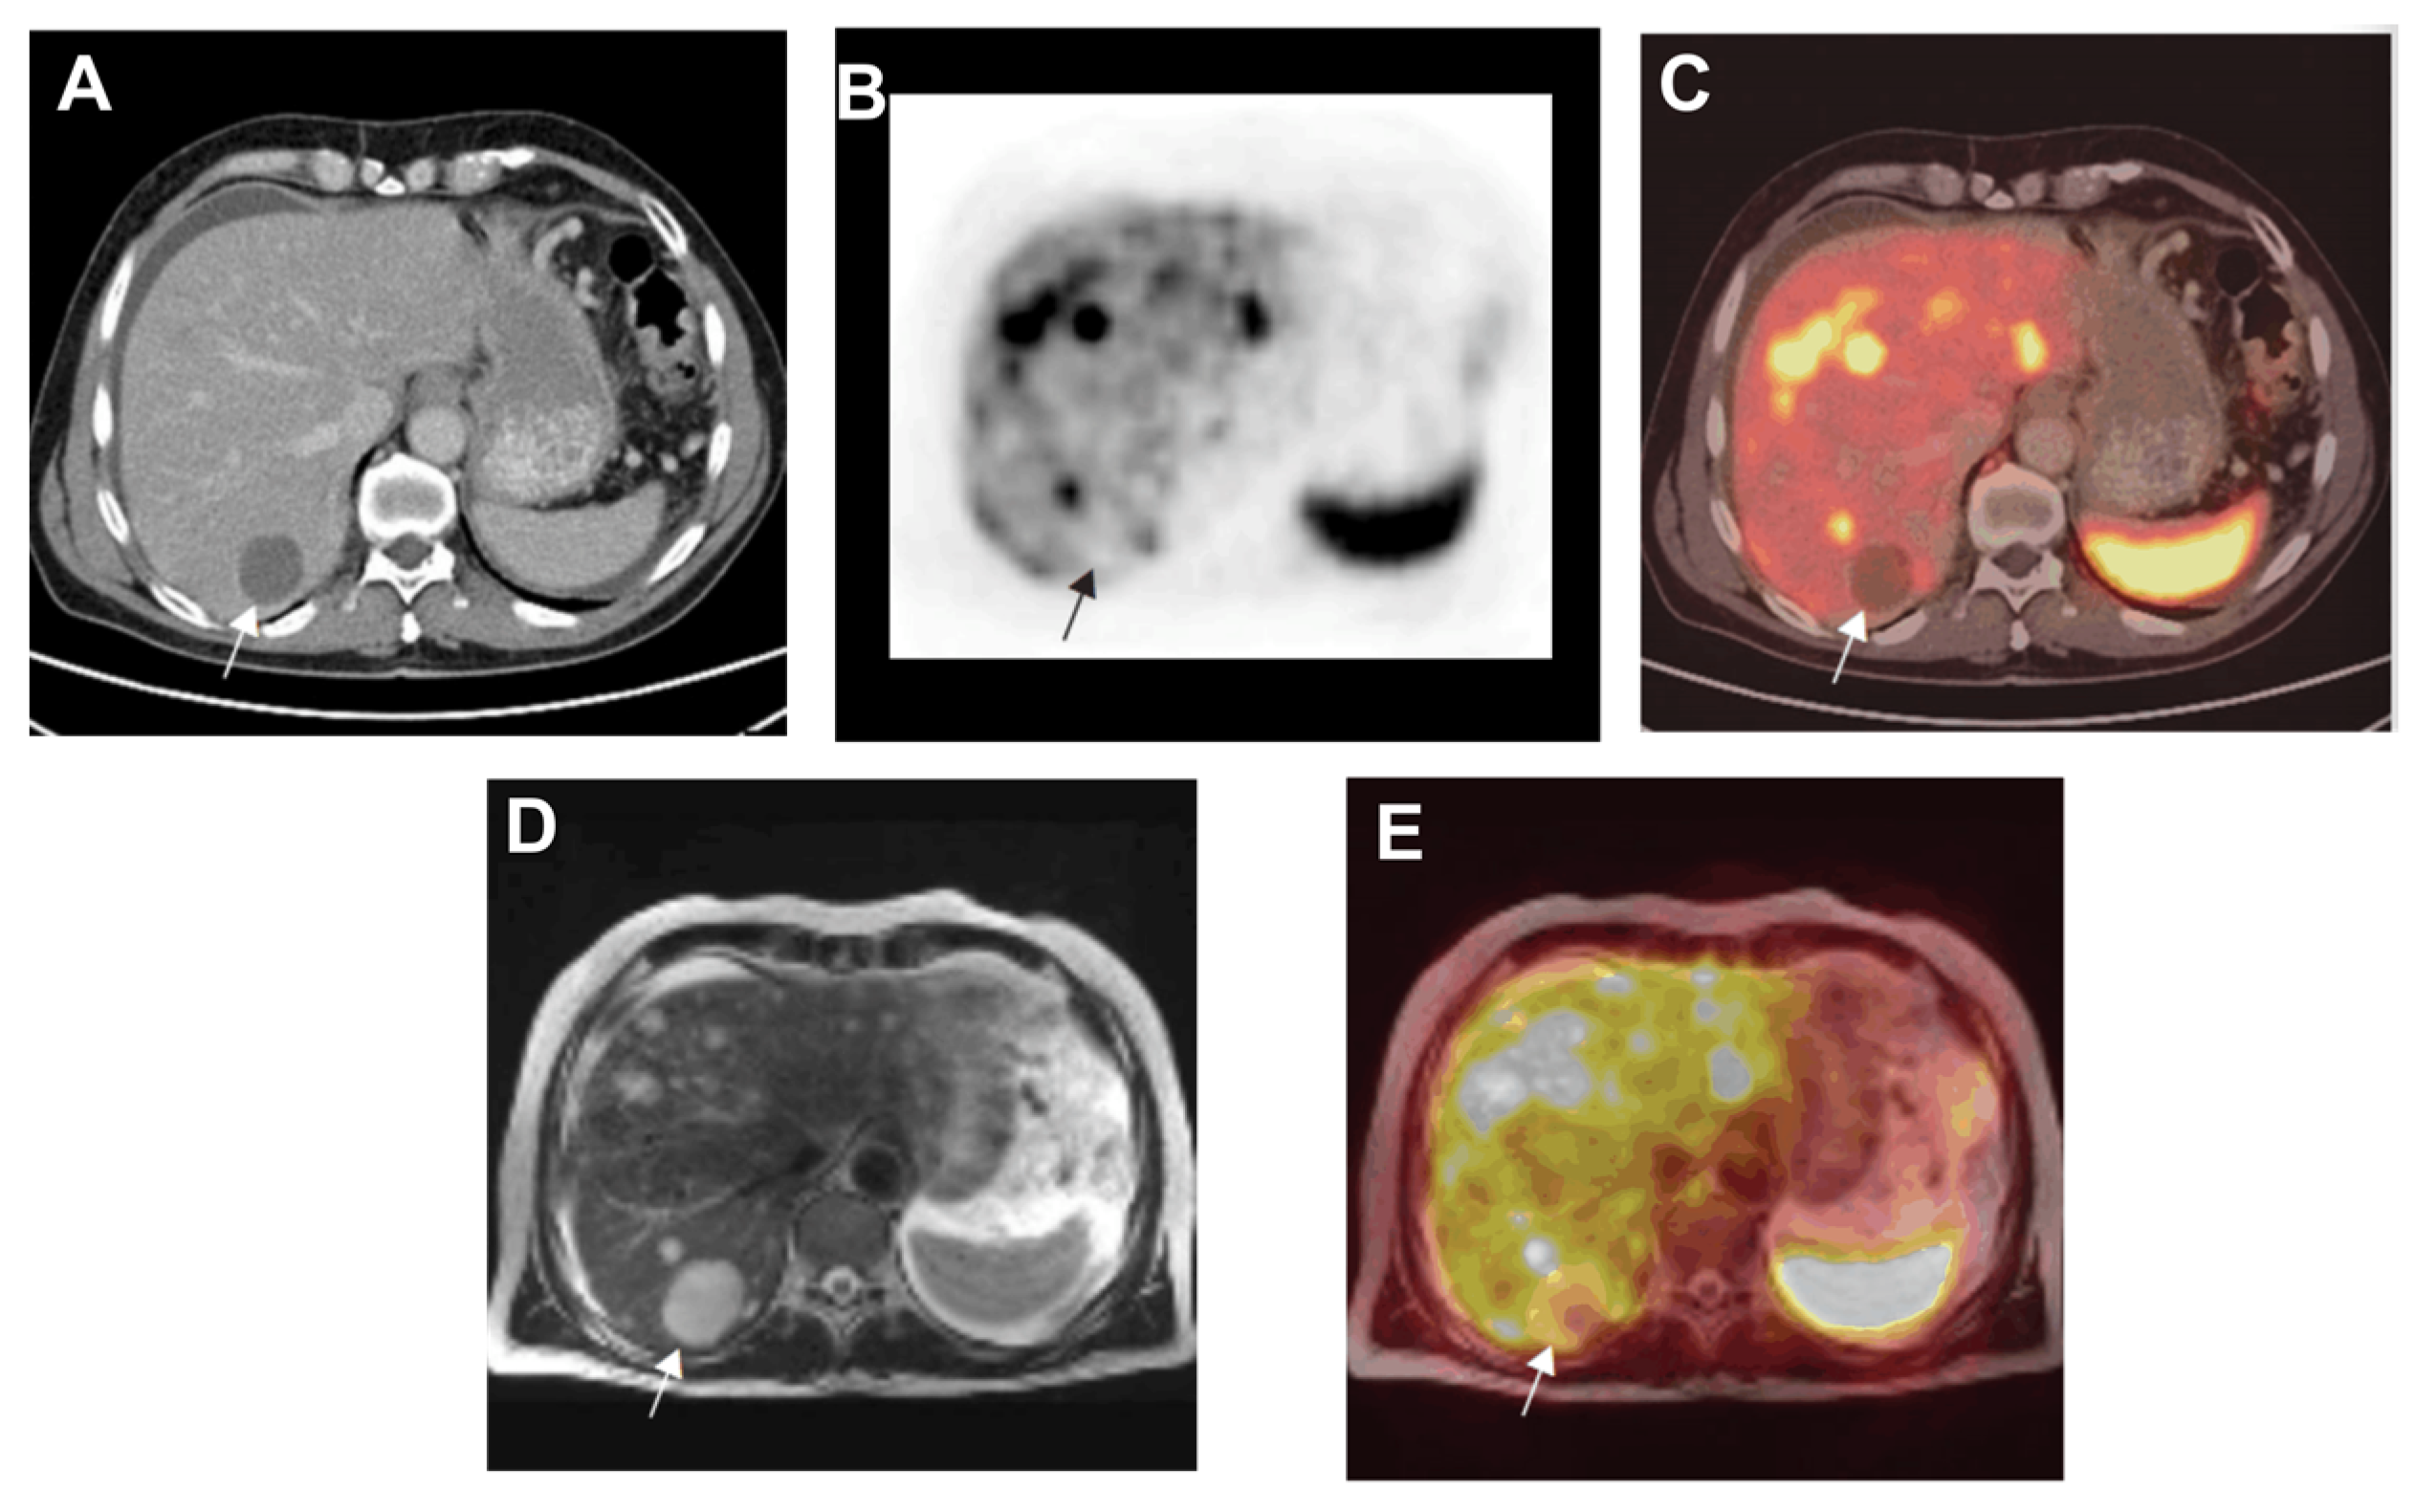

- Seemann, M.D.; Meisetschlaeger, G.; Gaa, J.; Rummeny, E.J. Assessment of the extent of metastases of gastrointestinal carcinoid tumors using whole-body PET, CT, MRI, PET/CT and PET/MRI. Eur. J. Med. Res. 2006, 11, 58–65. [Google Scholar]

- Bader, T.R.; Semelka, R.C.; Chiu, V.C.Y.; Armao, D.M.; Woosley, J.T. MRI of carcinoid tumors: Spectrum of appearances in the gastrointestinal tract and liver. J. Magn. Reson. Imaging 2001, 14, 261–269. [Google Scholar] [CrossRef]

- Maccioni, F.; Almberger, M.; Bruni, A.; Parlanti, S.; Marini, M. Magnetic resonance imaging of an ileal carcinoid tumor correlation with CT and US. Clin. Imaging 2003, 27, 403–407. [Google Scholar] [CrossRef] [PubMed]